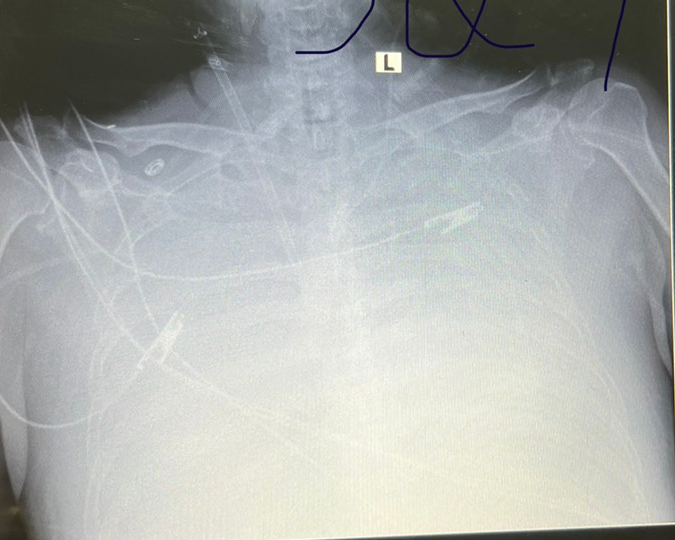

Hình ảnh Xquang phổi ngày 30/5